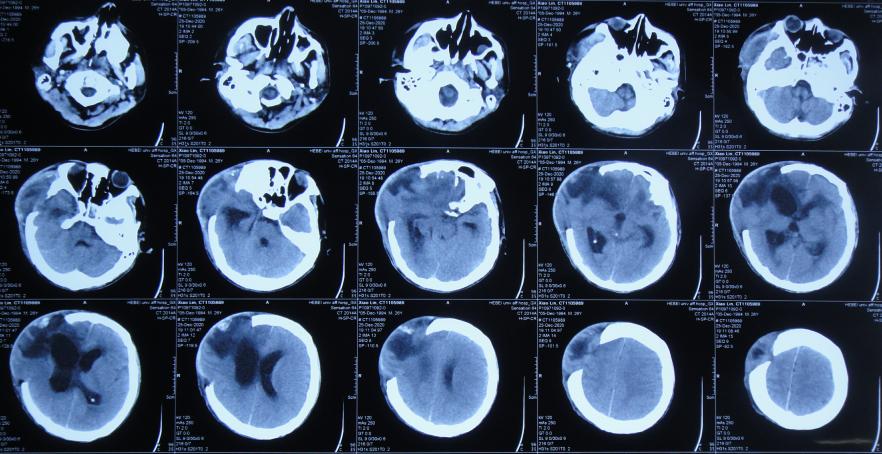

患者于2020年12月12日,在工作时意外从货车上摔下致头颅受伤,出现意识不清,送至河北省定兴县某医院,急诊查头颅CT示颅内血肿,中线有偏移( 图-1 ),给予开颅颅内血肿清除术+去骨瓣减压术,留置引流管,并行气管切开术;术后当天查头颅CT示开颅术后状态( 图-2 ),转入ICU病房。

图-1: 2020年12月12日头颅CT